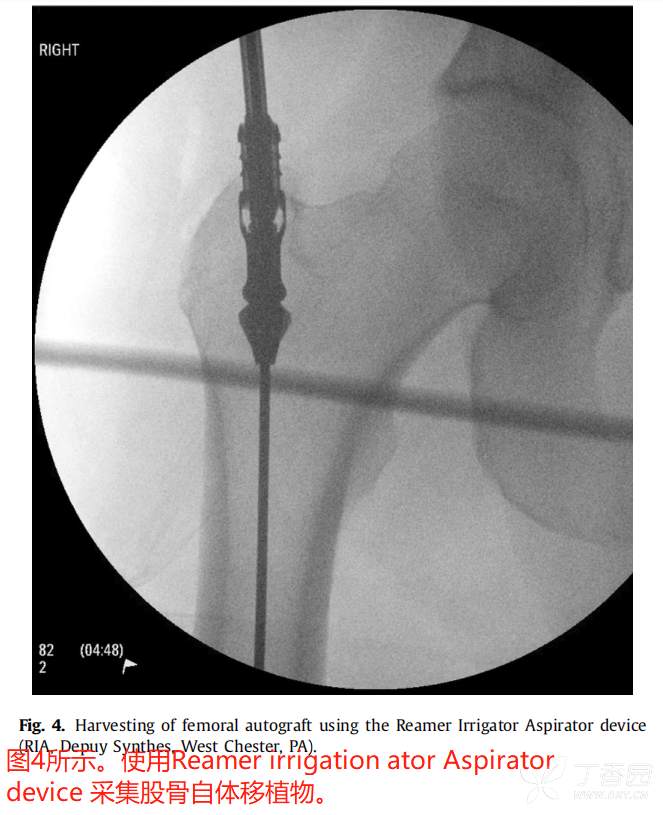

最近,国外采用Reamer灌洗吸引器系统(RIA, Depuy Synthes, West Chester, PA)从股骨髓腔进行扩孔已经成为一种常见的松质移植物来源。

在一项尸体研究中【3】,Finnan等人得出结论:无论是转子、“梨状窝”,还是逆行钻孔,用RIA扩孔后股骨的机械强度仍足以允许无支撑的单腿负重。但从另外一个尸体研究表明,这一过程仍然会有骨折风险,说明这是一个潜在的并发症。【4】

在一些研究中,RIA技术的结果与更传统的髂骨移植进行了比较。Belthur等报道使用RIA后愈合率为90%,而髂骨移植后愈合率为80%。【5】此外,在本研究中,RIA组的疼痛评分较低,但髂嵴骨移植物摘除术后并发症发生率较高。